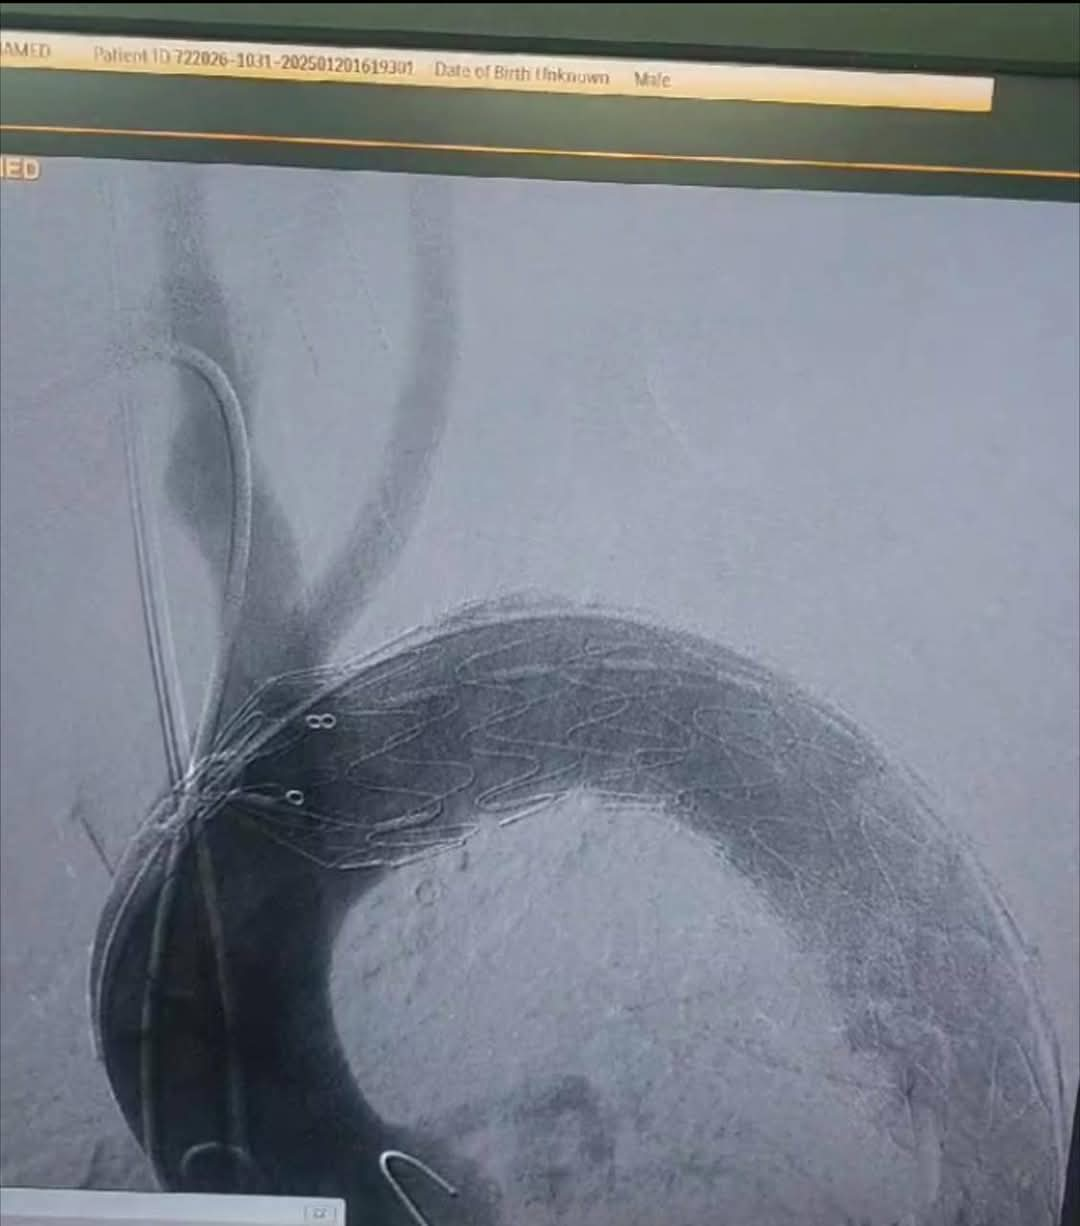

أجرى فريق أطباء قسم جراحة الأوعية الدموية بمستشفي مصر للطيران عملية إصلاح انشطار بالشريان الأورطي الصدري ممتد من الشريان تحت الترقوة الأيسر إلى شريان الحوض والفخذ الأيسر عن طريق استخدام الدعامات المغطاة Ankura™️ لتثبيت الشريان الأورطي الصدري واستعادة تدفق الدم الطبيعي.

وتم استخدام تقنية جديدة تحتاج الي مهارة ودقة عالية وللمرة الأولى في مستشفي مصر للطيران وهي عمل دعامة مغظاة فرعية لشريان الطرف العلوي الأيسر TEVAR + In situ fenestration for LSA + LSA stenting للحفاظ علي الدورة الدموية بالطرف العلوي الأيسر عن طريق عمل فتحة بالدعامة المغطاة بالشريان الأورطي الصدري باستخدام إبرة ( Futhrough™️ ) للحفاظ علي تدفق الدم بواسطة القسطرة التداخلية.